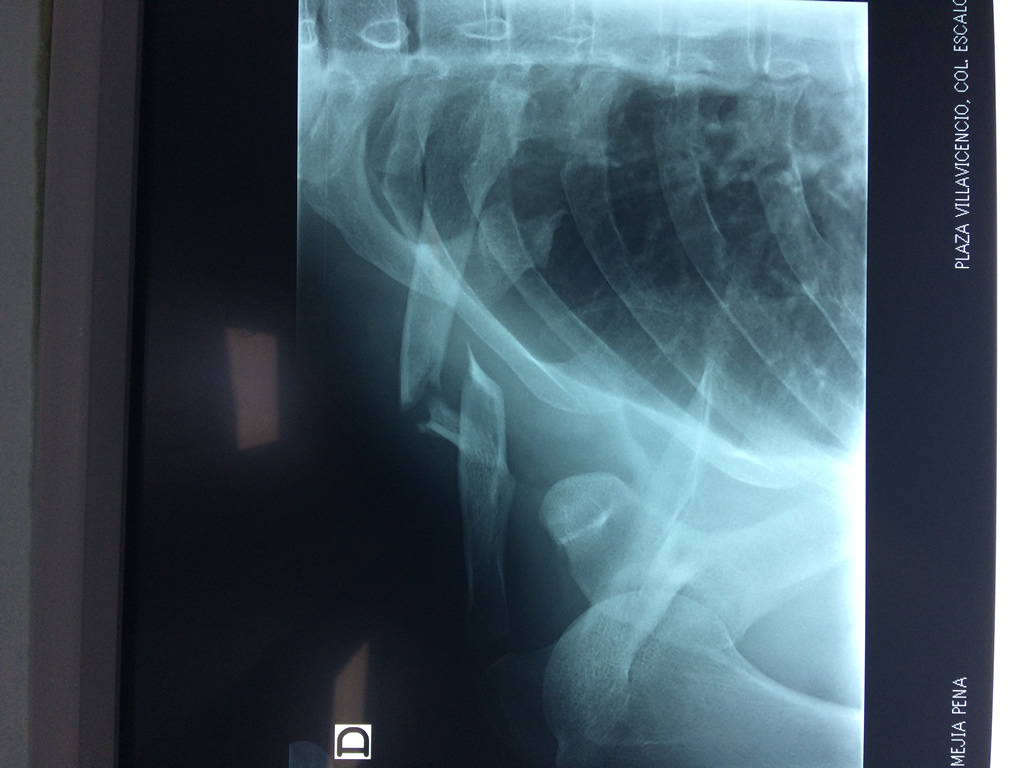

Cirugias en El Salvador - Clavícula

La clavícula es un hueso largo, con forma de "S" itálica, situado en la parte anterosuperior del tórax. Junto con la escápula forman la cintura escapular. Se puede palpar por toda su longitud y se extiende del esternón al acromion de la escápula, siguiendo una dirección oblicua lateral y posterior.